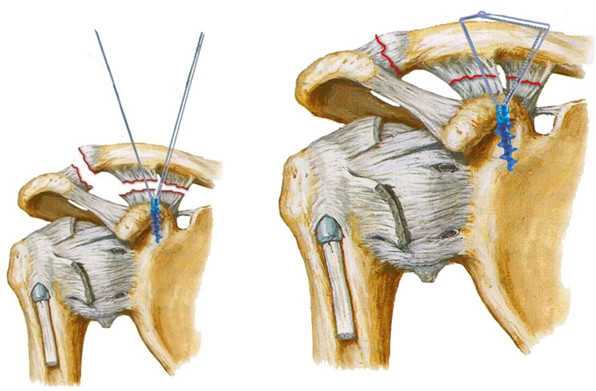

Методика MINAR

Методика MINAR (Minimally Invasive Acromioclavicular Reconstruction) данная методика выполняется через разрез длинной 3-4 см, происходит фиксация ключицы двумя металлическими пуговицами и очень прочной нитью. Принцип метода заключается в том, что фиксаторы располагаются так, чтобы вектор силы повторял ход порванных связок.

Данный метод сохраняет нормальную подвижности ключицы и обеспечивает высокий стабилизирующий эффект. В послеоперационном периоде необходима иммобилизация руки косыночной повязкой в течении 3-х недель. Так же пациент получает физиотерапевтическое лечение, реабилитационные мероприятия.

Методика MINAR® Mинимально Инвазивная Aкромиально-ключичная Реконструкция — малоинвазивный метод хирургического лечения вывиха акромиального конца ключицы в Клинике на Комарова.

Методика MINAR является наиболее ярким представителем целого направления операций, в которых используется один и тот же принцип: фиксатор располагают так, чтобы вектор силы повторял ход порванных связок. Раньше эту операцию выполняли с использованием лавсановых нитей (лавсанопластика), но сейчас появились более современные материалы. Например, возможна пространственная реконструкция с помощью якорных фиксаторов.

Операции можно выполнять под артроскопическим контролем, который означает, что точное расположение фиксатора врач контролирует через тонкую видеокамеру (артроскоп).